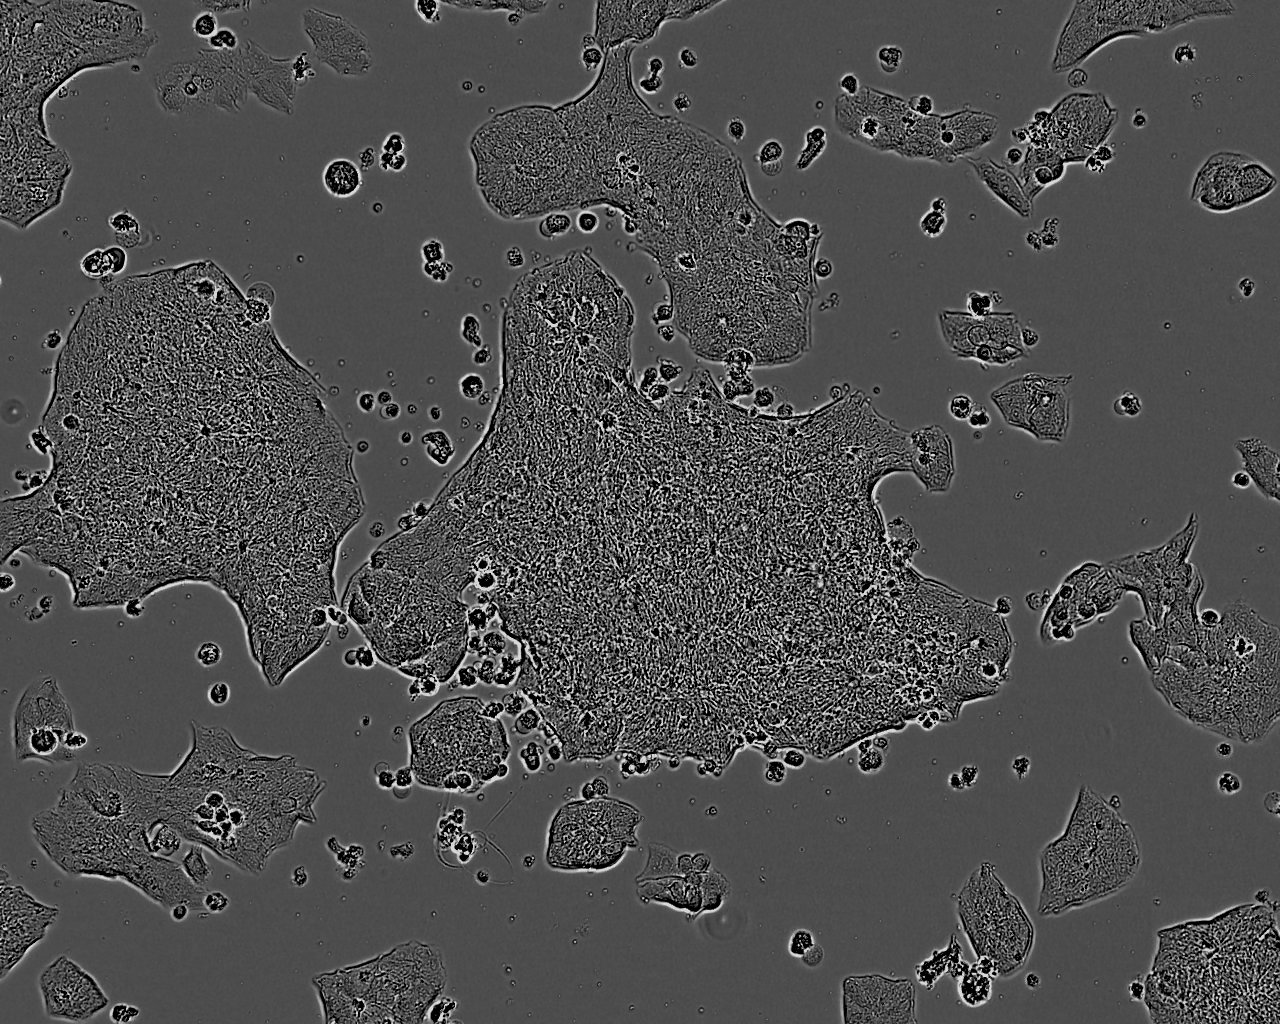

细胞形态:上皮细胞样

细胞生长:贴壁

细胞背景资料:1979年建系;这株细胞源自一位56岁女性胃腺癌患者的淋巴结转移灶。RPMI-1640培养12天,细胞开始生长,首次传代10天;31个月中传代186代。免疫抑制的ICR小鼠、乳犬皮下移植成功,家兔、乳犬眼前房移植成功;淋巴结转移,从小鼠皮下侵袭至肌层。

细胞生长特性:贴壁生长